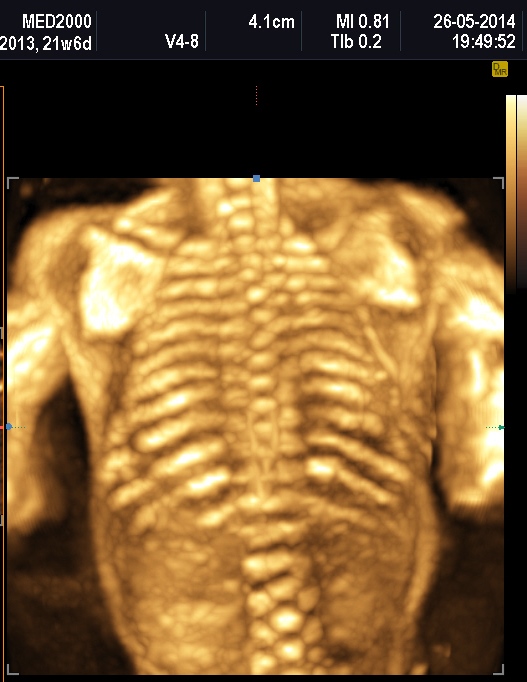

Quella che interessa dal punto di vista della diagnosi ecografica prenatale è l'Osteogenesi Imperfetta tipo II (OMIM 166210) caratterizzata da fragilità ossea con fratture multiple, micromelia severa dovuta alle fratture delle ossa lunghe, ipoplasia toracica severa a volte con fratture costali, ipomineralizzazione diffusa del cranio.  Ecograficamente si manifesta con ossa corte, ricurve e fratturate (le ossa fratturate si presentano angolate); ossa craniche scarsamente ossificate (tanto che la volta cranica può avere una ecogenicità simile a quella della linea mediana) con conseguente migliore evidenza e definizione delle strutture cerebrali e segno caratteristico la deformabilità della teca cranica.;  ipoplasia toracica con fratture costali; IUGR; movimenti fetali scarsi.